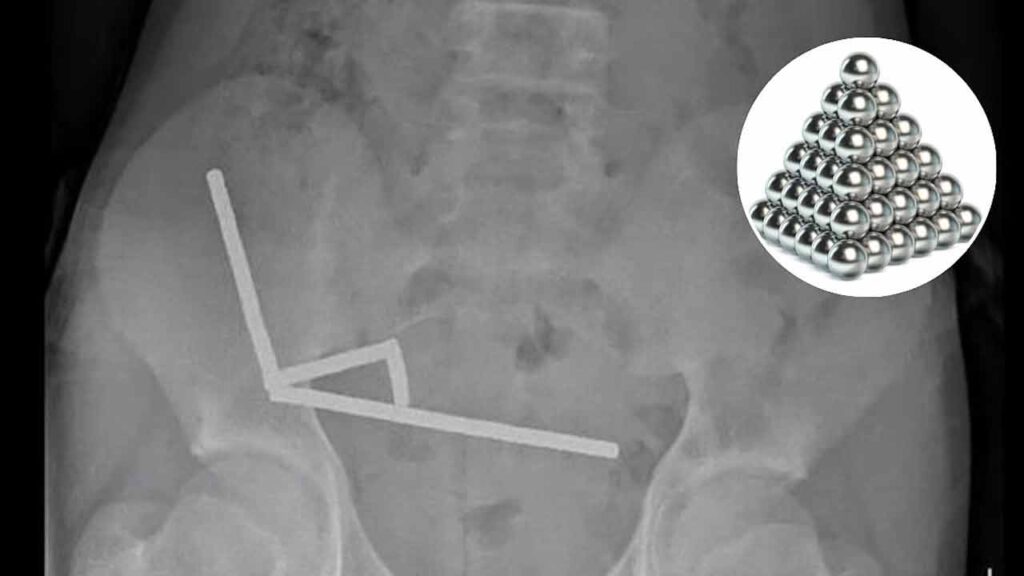

బాలుడి కడుపులో కుప్పలు కుప్పలుగా అయస్కాంతాలు( Magnets ) ఉన్నట్లు నిర్ధారించారు డాక్టర్లు. ఆ అయస్కాంతాలన్నీ పేగుల్లో ఉండిపోయినట్లు వైద్యులు కనుగొన్నారు. ఇక ఏ మాత్రం ఆలస్యం చేయకుండా బాలుడికి వైద్యులు సర్జరీ నిర్వహించారు. అనంతరం 100 అయస్కాంతాలను తొలగించారు. ఈ అయస్కాంతాల వల్ల పేగుల్లోని కొంత భాగం డ్యామేజీ అయింది. దీంతో పాడైన పేగు భాగాన్ని తొలగించి బాలుడి ప్రాణాలను కాపాడారు. బాధితుడు ప్రస్తుతం ఆరోగ్యంగా ఉన్నట్లు డాక్టర్లు పేర్కొన్నారు.